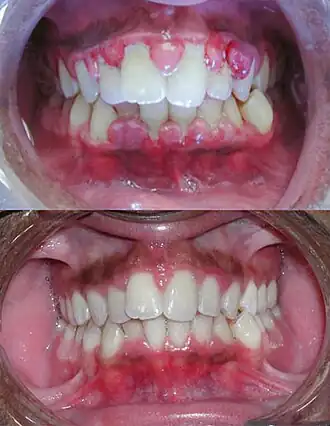

Gengivite severa antes do tratamento na imagem de cima e depois do tratamento por debridamento mecânico na imagem de baixo.

Gengivite é o processo inflamatório que ocorre na gengiva que geralmente decorre do acúmulo de placa bacteriana, também chamada de biofilme dental, devido a falta de higiene bucal adequada do indivíduo e pode estar relacionada ao estado imune do indivíduo em alguns casos. A irritação tecidual provocada pela placa bacteriana tem como principais características a alteração da coloração da gengiva que se torna avermelhada, também apresentando textura e forma alteradas. Entretanto o sangramento tende a ser o sinal mais evidente desta condição inflamatória. Pode ocorrer sangramento à sondagem realizada pelo profissional durante a consulta de diagnóstico, todavia não é incomum que o indivíduo perceba a presença do sangramento ao realizar a escovação dentária e/ou ao passar o fio dental na região interdentária.[1]

Devido ao fato da gengivite não existir sem um grupo bacteriano envolvido, o seu tratamento se resume ao aumento da higienização bucal do hospedeiro, visando controlar a formação de placa-bacteriana nos dentes. Em casos onde o indivíduo sofre de alguma imunodeficiência, é de suma importância que seja feito o acompanhamento com um dentista, para que assim uma limpeza profunda possa ser feita.